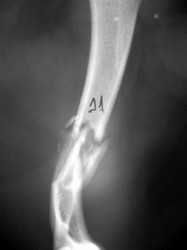

PRÁCTICAS CURSO DE FIJACIÓN EXTERNA PERFECCIONAMIENTO.

Húmero.